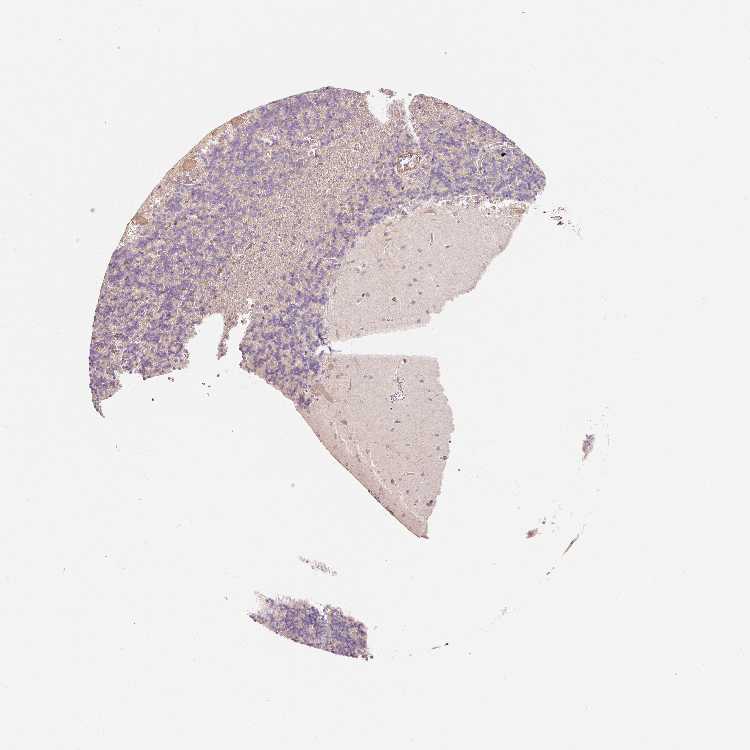

CEREBELLUM - Antibody stainingi

Antibody staining in the annotated cell types in the current human tissue is reported as not detected, low, medium, or high, based on conventional immunohistochemistry profiling in selected tissues. This score is based on the combination of the staining intensity and fraction of stained cells.

Each image is clickable and will lead to virtual microscopy that enables deeper exploration of all samples and also displays staining intensity scores, fraction scores and subcellular localization as well as patient and tissue information for each sample.

Antibody HPA052426Antibody HPA052428Antibody HPA061371

Purkinje cells MediumMediumLow

Cells in granular layer Not detectedHighNot detected

Cells in molecular layer Not detectedLowNot detected